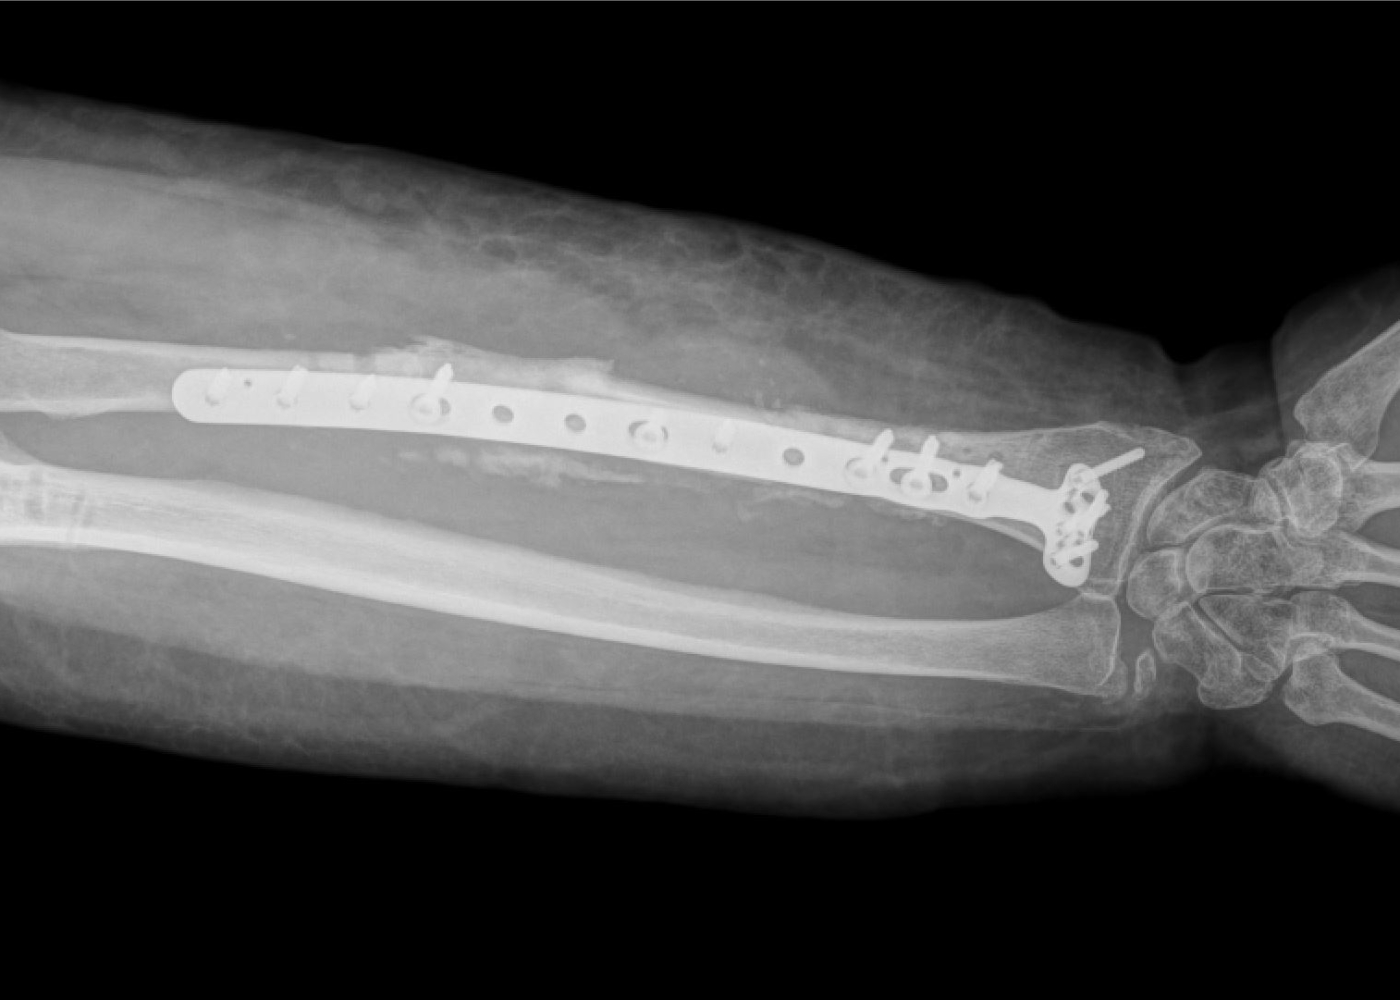

Երկրորդ վիրահատությամբ Միկրովիրաբուժության ծառայության ղեկավար Արթուր Մամբրեյանի և բժիշկ Սուրեն Թոփլաղալցյանի կողմից սրունքից վերցվել է ոսկրային տրանսպլանտանտ իր զարկերակով, որը միացվել է նախաբազկի զարկերակին։

Միաժամանակ, Օրթոպեդիայի և վնասվածքաբանության ծառայության ղեկավար Ատոմ Տեր-Գրիգորյանի, բժիշկներ Տիգրան Կուպալյանի և Խաչատուր Հարությունյանի կողմից կատարվել է ճաճանչոսկրի օստեոսինթեզ՝ մետաղական հատուկ հարթակի և պտուտակների օգնությամբ, որի վրա ֆիքսվել է ոսկրային դեֆեկտի հատվածում տեղադրված տրանսպլանտանտը։

Վիրահատությունից երեք շաբաթ անց արդեն բուժառուի ձախ ձեռքի ֆունկցիան վերականգնվել է, ունենք դրական դինամիկա։